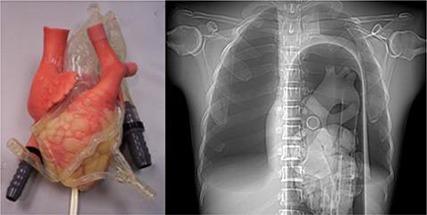

An anthropomorphic beating heart phantom for cardiac x-ray CT imaging evaluation.

The current work describes an anthropomorphic beating heart phantom constructed as a tool for the assessment of technological advances in cardiac x-ray computed tomography (CT). The phantom is comprised of a thorax, a compressor system, an ECG system, a beating heart with tortuous coronary arteries, and the option to add or remove pathologies such as aberrant beats, stents, and plaques. Initial trials with the phantom have shown its utility to assess temporal resolution, spatial resolution, radiation dose, iodine contrast, stents, and plaques.